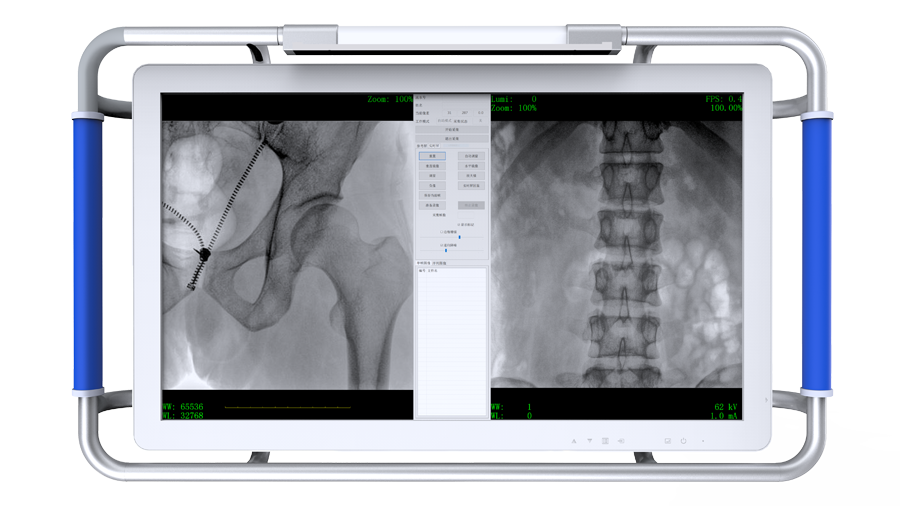

平板尺寸升級 呈現(xiàn)更多解剖細節(jié)

采用30CM×30CM大尺寸動態(tài)平板探測器,成像面積較傳統(tǒng)平板探測器大幅提升。

圖像清晰細膩

高清像素,低信噪比,細小的組織結構也可以清晰顯示。

專業(yè)觸控屏

●屏幕內置DICOM醫(yī)學曲線,幫助辨認細微組織的密度變化。

●27英寸大尺寸顯示器,更大視野,方便觀察微小結構。

●一屏雙顯,可同時觀察正側位圖像,便于對比觀察。

Clinical picture

臨床圖片